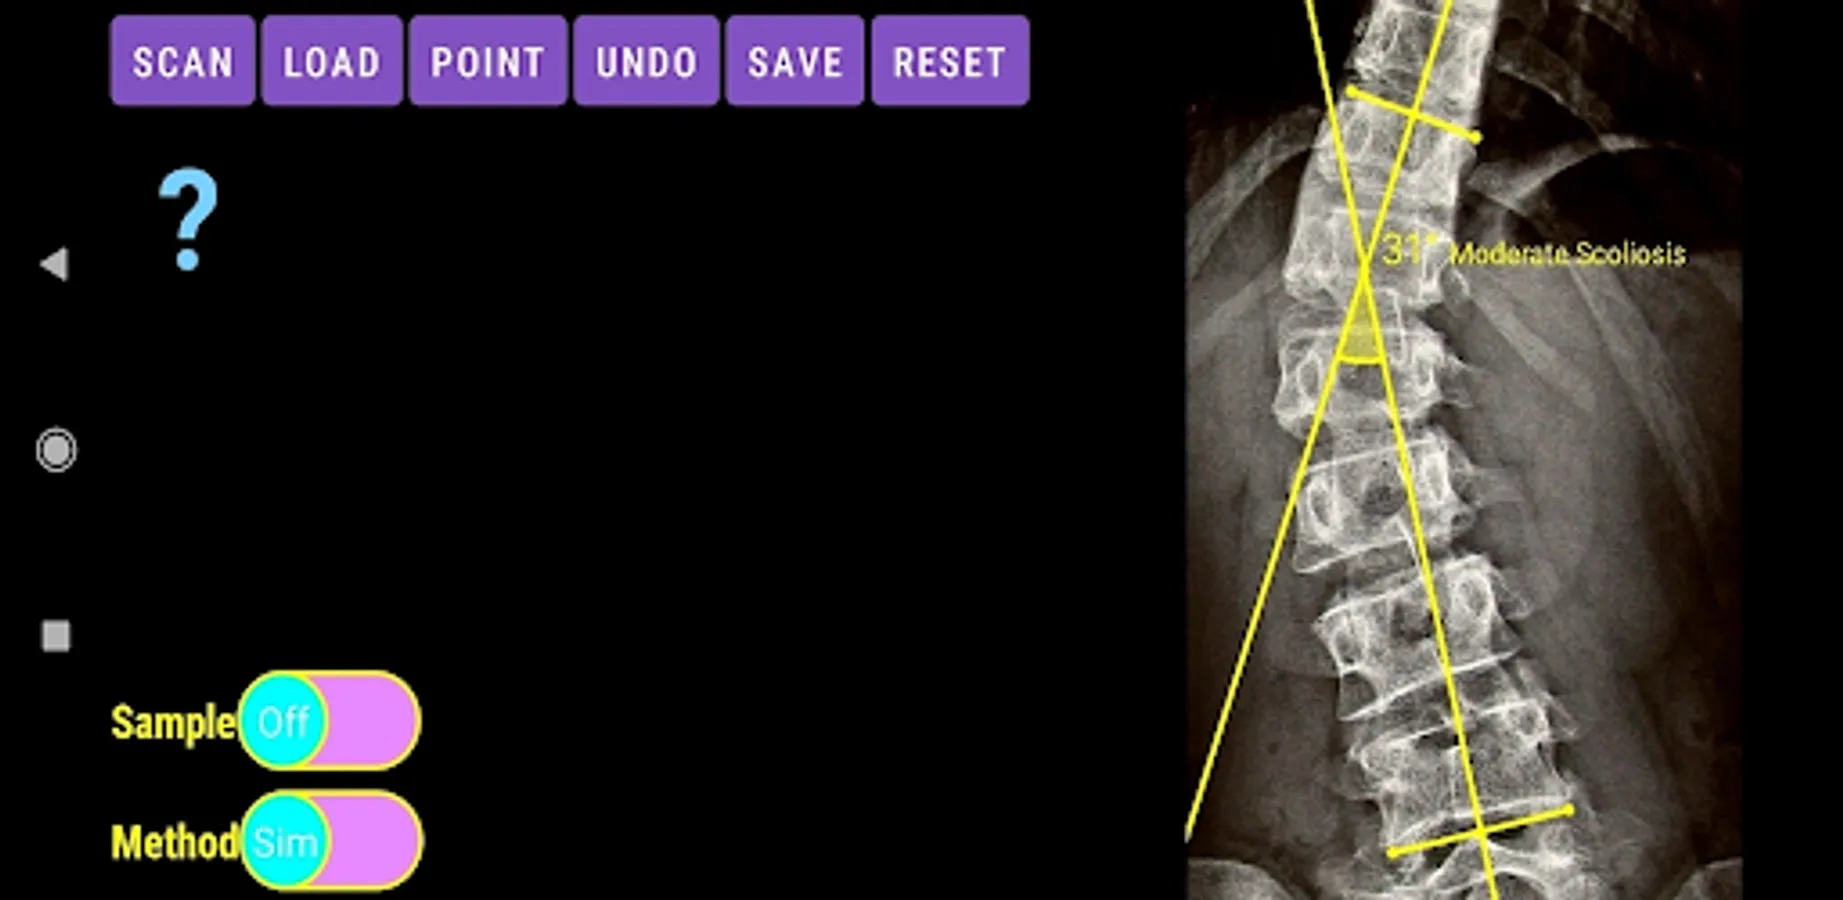

The app offers a very convenient way to asses spinal deformity by measuring the Cobb angle. The first thing is to load one image from your photo library or capture a photo from x-rays photos of a patient. The app offers two measuring methods, the simple (Sim.) and the extended (Ext.). By clicking the relevant option, the option is highlighted and the respective method is activated.

-Offers a very convenient way to determine the most accurate possibly way at once. By marking four points at the same X-ray, at each spine the App calculates the Cobb angle. In cases where values are out of normal ranges, the scoliosis is categorized according to measured angle as mild, moderate, severe. To simplify the process and to minimize inter-observer errors usually by not selecting the actual end vertebra, the app offers also in ext mode the ability to draw the vertical reference line through the patient’s sacrum and to identify more easily the end vertebrae (ext method).